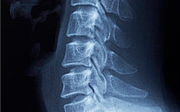

X-ray

CT, MRI

영상의학과 검사